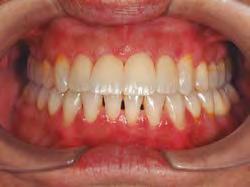

–Corticotomías y Ortodoncia. Ampliando límites del movimiento dental, por la Dra. Aranzazu Senosiain y cols. [50]

–Tratamiento de un caso de Ortodoncia y Cirugía Ortognática con placas preformadas y tecnología 3D, por la Dra. Elena Bonilla Morente y cols. [62]

–Uso del anclaje esqueletal como alternativa eficiente en el manejo ortopédico de clases III por deficiencia de maxilar superior, por el Dr. Carlos Becerra y cols. [74]

–MARPE, una alternativa a la disyunción en el paciente adulto, por el Dr. Enrique Solano y cols. [88]